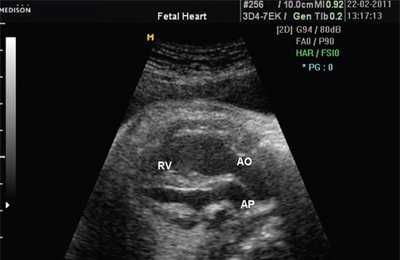

В равной степени это относится к дефекту межжелудочковой перегородки (рис. 6), простой форме транспозиции магистральных сосудов (рис. 7, 8), транспозиции магистральных сосудов с дефектом межжелудочковой перегородки (синдром Тауссиг - Бинга) (рис. 9), общему желудочку (рис. 10), общему артериальному стволу (рис. 10), двойному отхождению сосудов от одного из желудочков сердца (рис. 11).

Рис. 9. Синдром Тауссиг - Бинга. Легочная артерия (отмечена стрелкой) расположена над дефектом межжелудочковой перегородки.

Рис. 10. Общий желудочек с отхождением TRUNCUS ARTERIOSUS. Стрелками показано разделение TRUNCUS ARTERIOSUS на аорту и ствол легочной артерии.

LV и RV - левый и правый желудочек, АР - легочная артерия, АО - аорта, VSD - дефект межжелудочковой перегородки.